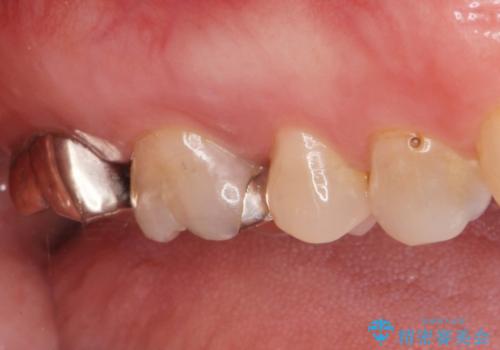

手前の歯はセラミック治療を行い、奥の歯は精密根管治療を行いゴールドクラウンで治療を行いました。

セラミックインレーは古い材料を拡大鏡でしっかり取り除き適合の良い詰め物が装着されました。